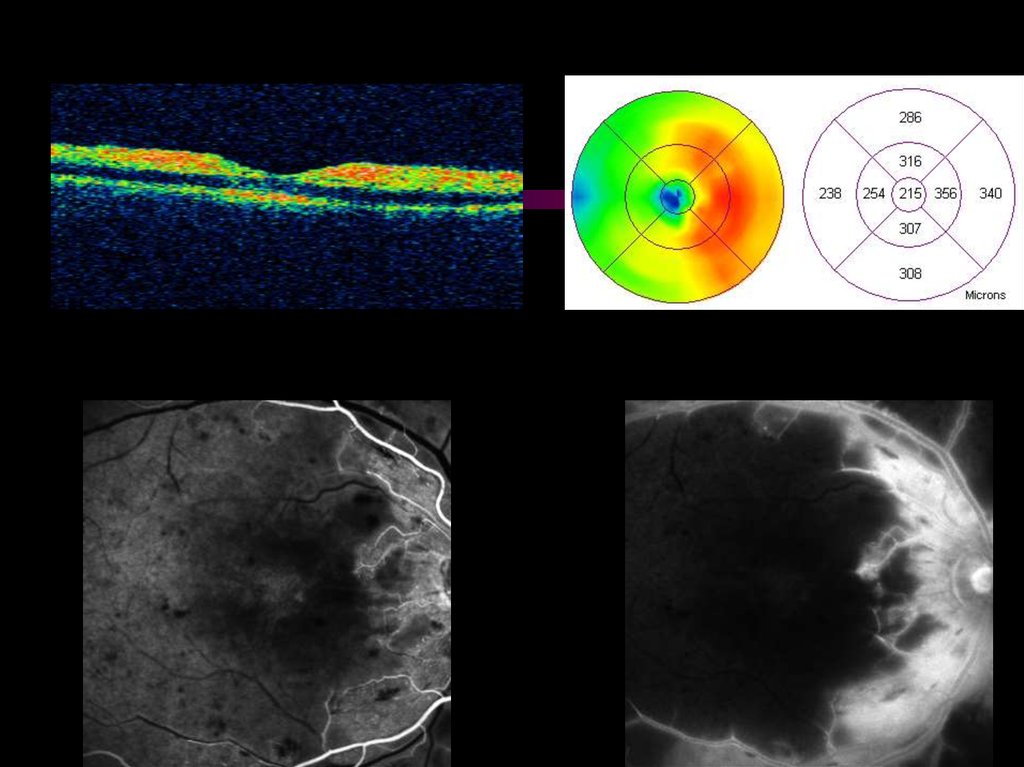

28. НЕПРОЛИФЕРАТИВНАЯ РЕТИНОПАТИЯ С МАКУЛЯРНЫМ ОТЕКОМ толщиной менее 400* микрон

• стандартное офтальмологическое обследование;

• дополнительно - оптическая когерентная томография

(ОКТ), периметрия - макулярный тест, флюоресцентная

ангиография (ФАГ)**.

• фокальная и/или по типу «решетки» лазеркоагуляция

сетчатки;

• повторный осмотр через 2-3 месяца с обязательным ОКТконтролем.

* для томографа OCT-STRATUS 3000, «ZEISS»;

29. НЕПРОЛИФЕРАТИВНАЯ РЕТИНОПАТИЯ С МАКУЛЯРНЫМ ОТЕКОМ

до коагуляции Vis=0.5

через 7 месяцев Vis=0.8

30. НЕПРОЛИФЕРАТИВНАЯ РЕТИНОПАТИЯ С МАКУЛЯРНЫМ ОТЕКОМ толщиной более 400 микрон

• дополнительно - ОКТ, периметрия, ФАГ по необходимости;

• интравитреальное введение кристаллических стероидов*

(ИВВКС) или ингибиторов ангиогенеза (ИВВИА);

• фокальная (и/или по типу «решетки» лазеркоагуляция

сетчатки через 4 недели после ИВВКС и через 2 недели

после ИВВИА при ОКТ-контроле;

• повторный осмотр через 3-4 месяца с обязательным ОКТконтролем.